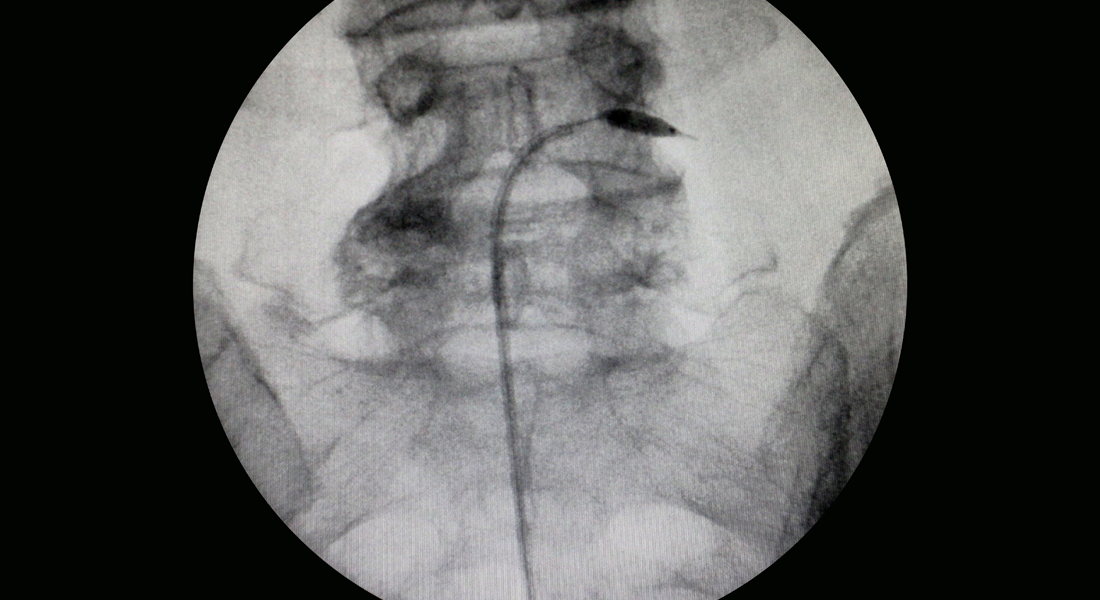

특수 카테터로 좁아진 척추관을 확장시켜 치료하는 비수술 요법

추간판 탈출로 신경이 압박되는 부분에 풍선 확장 기능이 포함된 특수 카테터를 이용하여 주변을 확장시켜 압박을 해소하고 통증을 없애는 치료법입니다. 확장과 함께 증상 호전에 도움이 되는 약물을 주입하여 효과적으로 통증을 완화할 수 있습니다.